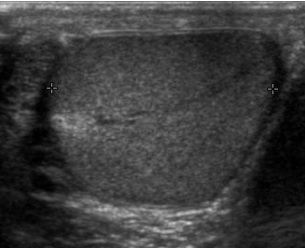

We provide ultrasound for males from the age of 16 onwards. The examination detects any lumps or bumps in the scrotum area, and is conducted by placing the transducer (probe) over this area.

During the examination, you will be asked to lower your trousers down to your knees and then lay on the couch. A sheet of paper is placed over the exposed area. Some gel is applied to the testicles and a transducer is scanned across the area in order to show images on the screen.